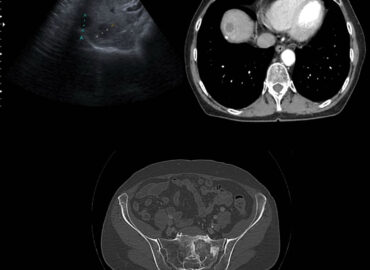

Paciente masculino, 32 años que consulta por tumoración a nivel de partes blandas localizado en flanco y FID. […]